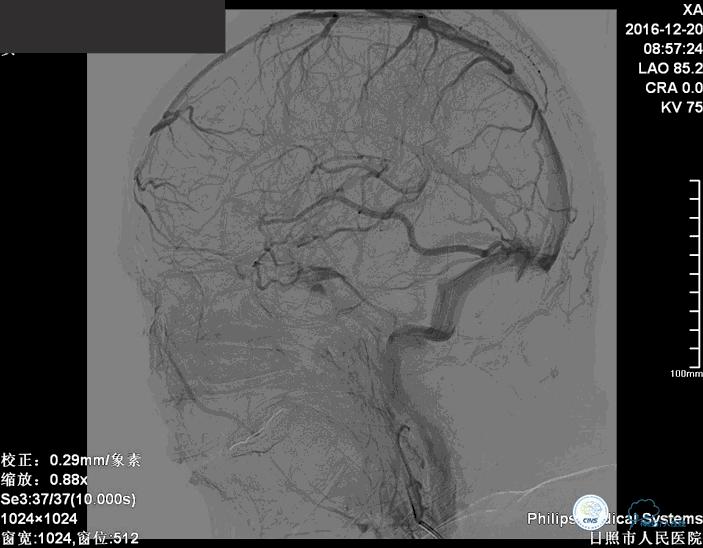

术后患者神志清楚,术后肢体运动较术前未见明显异常。

术后患者神志清楚,术后肢体运动较术前未见明显异常。双微管技术降低了患者治疗的费用。同时避免了支架置入以后,终生服用抗血小板药物的情况。